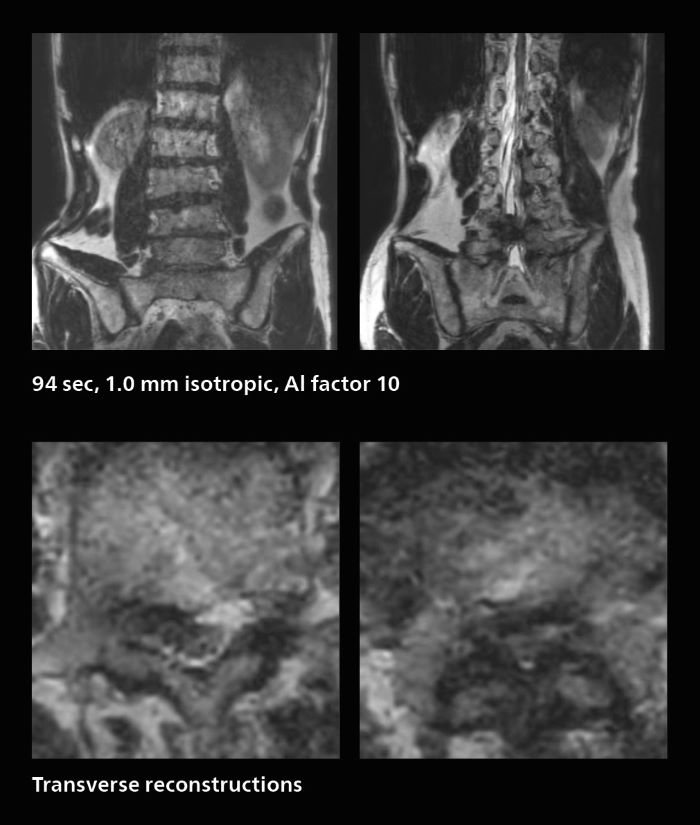

Fast lumbar spine imaging for successful exam of patient in pain

A patient arrived saying that undergoing MRI was not possible because of severe back pain and leg pain, was imaged with SmartSpeed in only 94 seconds. The scan was diagnostic and afterwards the patient confirmed that it only took a little while. Performed on Elition X.

Fast lumbar spine MRI with SmartSpeed of a patient in pain produced a successful isotropic diagnostic scan in only 94 minutes.

The hospital’s fast lumbar spine ExamCard includes T2W SpineVIEW, 1:40 min, 1.0 mm isotropic, acceleration factor 12.

Many patients who must undergo a lumbar spine examination suffer from back pain. For these patients it is difficult to maintain the imaging position long enough to successfully complete the examination. “In such cases, using SmartSpeed allows us to perform volume imaging, so that we acquire only one high resolution 3D sequence in a short time and then reconstruct the other orientations from that,” Dr. Katahira says.

“This is highly advantageous because the patient needs only endure a short exam time, whereas before it was necessary to acquire a larger number of sequences in total. We have seen that the shorter time has allowed us to scan patients who previously could not finish the exam. This is a great advantage.”